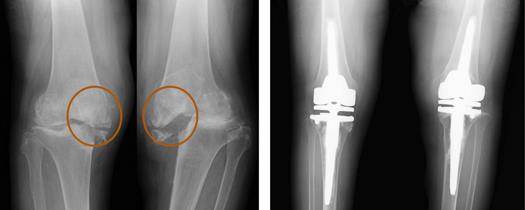

人工膝関節の中で最も多い手術です。下の左側のレントゲンを見ると、内側は、軟骨が消失<オレンジの三角>し、骨棘(刺のように飛び出ている骨〈青の矢印〉)が形成されています。外側は関節の隙間は保たれていますが、やはり骨棘が形成されています。このように内側、外側ともに変形がある時には、骨の表面を軟骨の代わりに金属で覆うようにします。これにより、歩行時の疼痛が改善し、ダンスやゴルフなどの趣味を続けることができます。(詳しくは「人工膝関節置換術について」を参照してください)

この方は高度な変形で靱帯機能不全と丸で囲んだ部分の骨が消失しています。これまで重症になりますと家の中を歩くのがやっとになります。このような場合は、欠損部に骨移植をおこない、靱帯の機能をもつ人工関節を使用します。片側だけ手術を行っても手術しない方の膝は不安定で痛みが強く、十分なリハビリができないと判断し、両側を同時に手術しました。当院ではこのように重度な変形の手術も行っております。